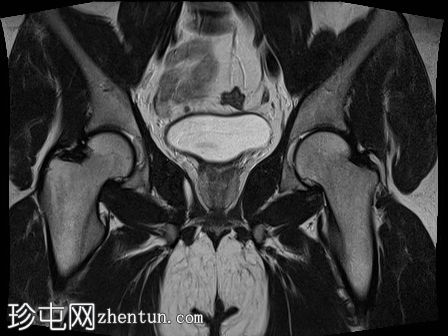

MRI

冠状位

T2加权像

双侧睾丸均未在阴囊内显露,而是位于盆腔腹股沟管上部。

-左侧睾丸大小为2.6 cm x 1.6 cm x 2 cm。

-右侧睾丸大小为2.6 cm x 1.2 cm x 1.1 cm。

双侧隐睾(睾丸未降)位于盆腔腹股沟管上部。